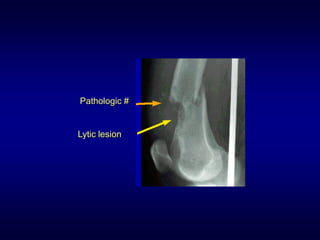

• Typical fractures

• Pathologic fractures

• Stress fractures

Pathologic #

Lytic lesion